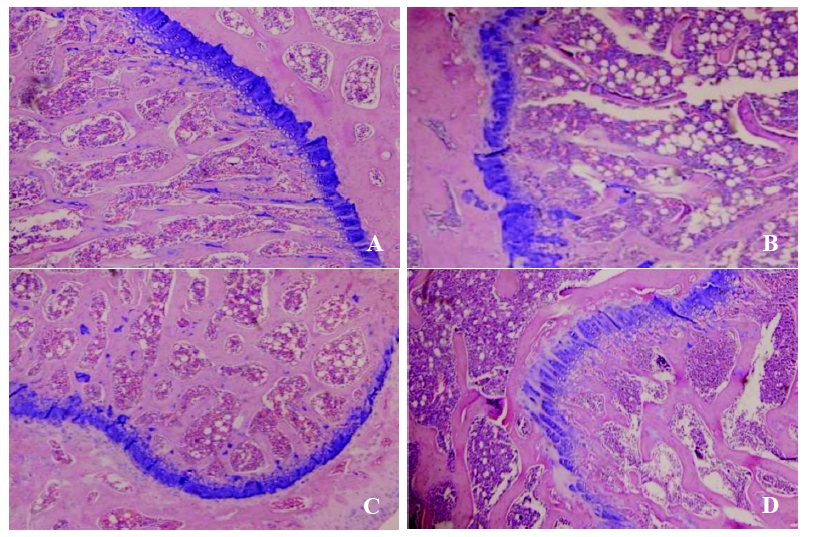

观察ZDF和SD大鼠动脉粥样硬化(atherosclerosis, AS)形成和AS组织中磷脂酶A2(cPLA2、sPLA2、LP-PLA2)的表达情况。

方法

取ZDF(fa/fa)大鼠和SD大鼠各6只,用高脂饲喂加小剂量多次腹腔注射7 ×10

5

U/kg维生素D3注射液,建立ZDF大鼠AS模型组和SD大鼠AS模型;另取ZDF(fa/+)大鼠和SD大鼠各6只,分别作为ZDF大鼠对照组和SD大鼠对照组,饲喂普通饲料。检测造模前后GLU、TC、TG、HDL-C、LDL-C的含量和造模后血清Ca

2+

含量,并取AS大鼠腹主动脉进行HE染色和cPLA2、sPLA2、LP-PLA2的mRNA表达检测。

结果

ZDF大鼠AS模型组和SD大鼠AS模型组的空腹血糖、血脂水平和血清Ca

含量均显著升高(P<0.01),腹主动脉出现典型的AS并伴明显的钙化,ZDF大鼠模型组血糖、血脂明显高于SD大鼠模型组,其AS病变也相对严重;ZDF大鼠AS模型组cPLA2和sPLA2的表达显著升高(P<0.01),LP-PLA2的表达显著降低(P<0.01); 而SD大鼠AS模型组cPLA2、sPLA2、LP-PLA2的表达均显著升高(P<0.01)。

结论

ZDF大鼠和SD大鼠进行高脂饲喂加小剂量多次注射维生素D3均能建立AS模型,ZDF(fa/fa)大鼠的AS病变相对严重,与其高血糖和高血脂状态有关;ZDF大鼠和SD大鼠中的PLA2的表达存在差异,这可能与SD大鼠AS形成的分子病理机制有关。